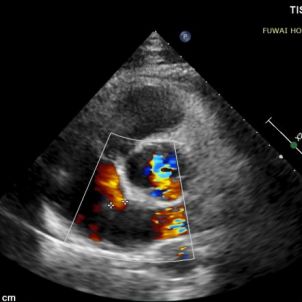

1. L'ASD era centrale nella posizione, con un diametro misurato di circa 8,1mm (vista bicavale) e 8,2mm (vista aortica ad asse corto).

1-day postoperative TTE revealed that the occluder is in good shape without residual shunt (see last figure).